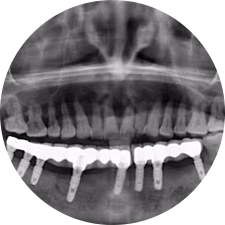

口腔種植是將人工牙根通過手術(shù)植入牙骨內(nèi),獲得牙槽骨牢固的支持,通過特殊的裝置和方式連接牙修復(fù)體,獲得與天然牙功能、結(jié)構(gòu)以及美觀相似的效果。

河北惟德口腔醫(yī)院擁有國內(nèi)豐富的半口/全口、即刻負重種植案例,十八年案例跟蹤分析,總結(jié)梳理出的各種不同類型的種植案例,Nobel種植體系針對半口/全口缺牙患者,通過4-8顆種植體可快速達到牙齒重建,不僅植入種植體較少,節(jié)省費用,手術(shù)時間更短。

術(shù)前患者CBCT口掃1:1三維重建,模擬手術(shù)過程及預(yù)測術(shù)后治療效果,確定每顆植體植入的適合的種植位點、深度及角度,有效避免損傷頜骨重要解剖結(jié)構(gòu),提高手術(shù)準(zhǔn)確度與安全性。

Noble口腔種植體系基本不受年齡限制,適用于缺牙修復(fù),也適用于牙槽骨萎縮、骨質(zhì)疏松、高血壓、糖尿病、超高齡的患者,即種即用,只需少量微小種植體,便可輕松微痛快速重建全口咬合,特殊力學(xué)設(shè)計,針對許多年紀(jì)較大,骨質(zhì)條件差,身體耐受力差的缺牙老人也能完成“即種即用”,受到廣泛好評。

惟德口腔種植體系是以患者感受為中心,取代傳統(tǒng)種植牙手術(shù)需要翻瓣、打孔、縫合,術(shù)前、術(shù)中、術(shù)后的繁復(fù)流程,采用3D導(dǎo)航微創(chuàng)準(zhǔn)確種植技術(shù),通過數(shù)字化CAD/CAM掃描技術(shù)獲得缺牙患者口腔數(shù)據(jù),以數(shù)據(jù)為基礎(chǔ)重建口腔模型進行模擬種植。